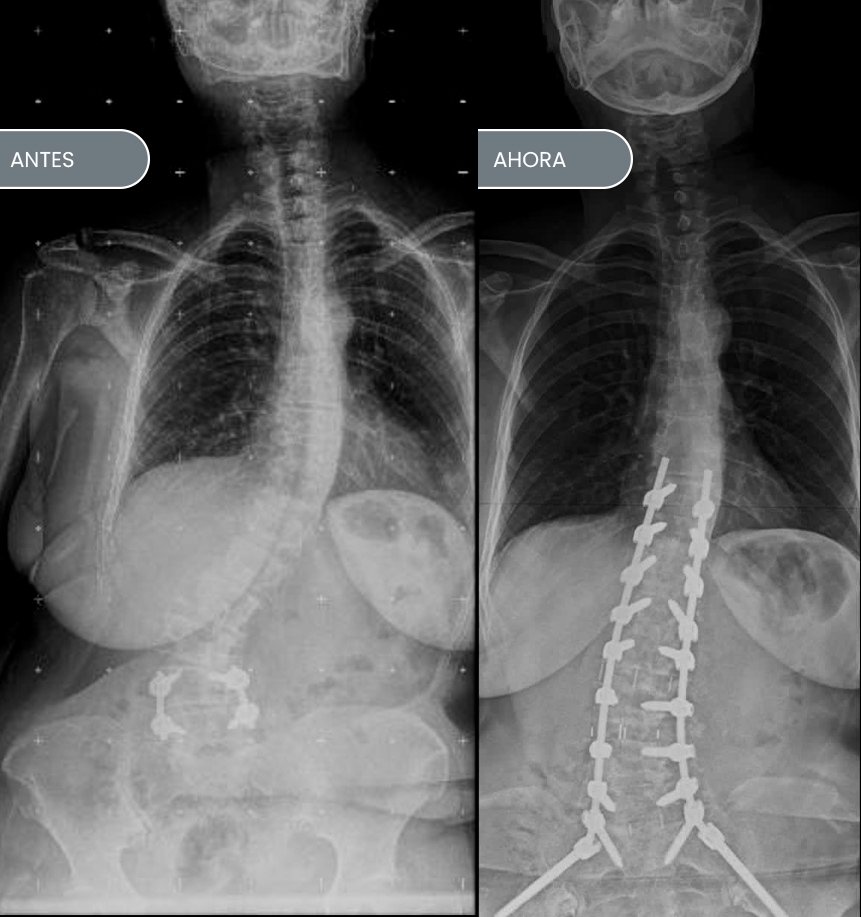

Primero el preoperatorio y luego los pasos intra. en este caso, la paciente estaba operada hacia 5 años y se lateralizó y quedó torcida. entonces le planifique la corrección en un día quirúrgico. bajo la misma anestesia le realizamos el abordaje lateral donde van las cajas. a continuación, la acuesto boca abajo y le colocamos todos los tornillos y barras para terminar la corrección. Esta paciente lleva operada 7 meses.

6 MESES DESPUÉS

ESCOLIOSIS IDIOPÁTICA

Siempre que se agotan o no resultan las opciones terapéuticas conservadoras (utilización de corsés o terapias físicas) y las curvas continúan aumentando su angulación. La cirugía de corrección es la opción correcta, se caracteriza por abordar por la espalda la curvatura escoliótica y colocar una serie de tornillos pediculares en cada una de ellas. Una vez colocados y bajo control radioscópico de guía y en conjunto con un médico neurólogo para monitorizar el funcionamiento de la médula espinal. Unimos, a través de dos barras conectoras cada uno de los tornillos. Se efectúan las maniobras de corrección de las curvas. Como bien sabemos, los patrones de curva cambian de paciente a pacientes. Es por eso que la indicación de instrumentación, más las maniobras de corrección varían de paciente a paciente. El espíritu de nuestro equipo es siempre el de restringir el número de vértebras instrumentadas para dar capacidad a las vértebras que están libres para ayudar a compensar el eje espinal y obtener un resultado óptimo.

Generalmente el procedimiento que se realiza bajo anestesia general y monitoreo neurológico, dura entre 3 y 4 horas. Y los pacientes deben permanecer internados durante 4 a 6 días. A veces se requiere de transfusiones sanguíneas que durante la preparación preoperatoria logramos utilizar del mismo paciente, lo que se llama auto donación. A las tres semanas pueden concurrir al colegio y se requiere de uso de analgésicos potentes los primeros 10 días.